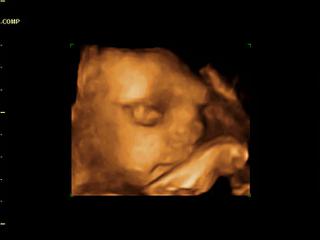

zabkaevka ja som bola na 4D v saci. urobil nam nejake videjka aj fotky ale sam povedal, ze je to menej kvalitne a to tym, ze mam placentu na prednej stene a tym je mala dost natlacena na placentu a je pred tvarickou menej plodovej vody. lebo cim viac je plodovej vody pred babom tym je kvalitnejsia fotka. ale nevadi aspon nieco mame a sme radi, ze je mala ok. pripajam fotecku.

no kiwi musím ti povedať, že sa na teba tvoja malá veľmi podobá. minimálne nosík má ako ty na fotke. 😀 veru nezaprieš ju 🙂 🙂 držte sa